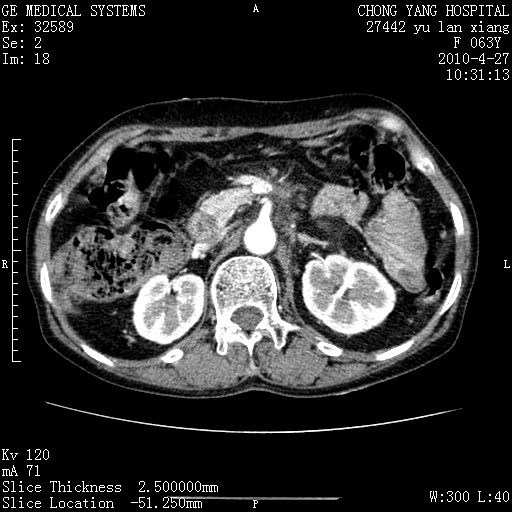

标题: CT26066:F63Y 上腹正中压痛半月,CA199:7400u/ml,MR示胰腺炎伴 [打印本页]

胰腺癌侵犯腹腔动脉干-分支、胃壁、左侧膈肌伴胰周及腹膜后淋巴结转移、胆囊切除术后。

胰腺癌侵犯腹腔动脉干-分支、胃壁、左侧膈肌伴胰周及腹膜后淋巴结转移、胆囊未显影。